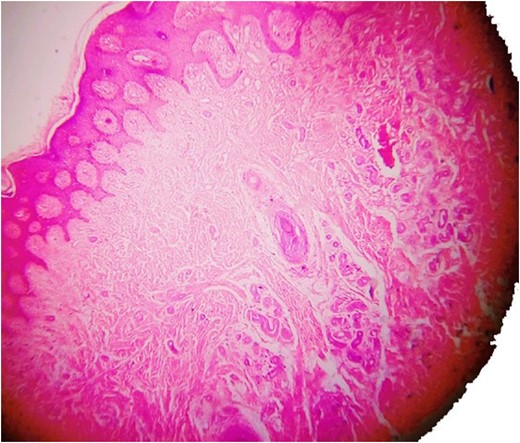

Haematoxylin and eosin staining showing eccrine angiomatous hamartoma.

Histopathology examination revealed grayish white to grayish brown lesions with hyperkeratitis of the epidermis and focally hyperplastic stratified squamous epithelium. Papillary dermis with numerous dilated, thin walled congested capillaries and the deep dermis with increased number of eccrine glands and numerous capillary channels intermingled with eccrine structure. The stroma was composed of fibrofatty tissue along with few pilar structures with the focal distribution of granulation tissue. Such a histological picture was found to be consistent with a diagnosis of EAKH.